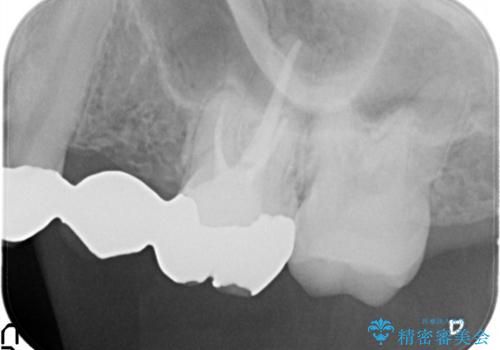

- 昔装着したかぶせ物が、不自然なのでやりかえたいとのことで来院されました。

前歯にレジン前装冠(保険内)が装着されており、自然な透明感がありません。

また奥歯にまたがるブリッジも金属のもので、適合もよくありませんでした。